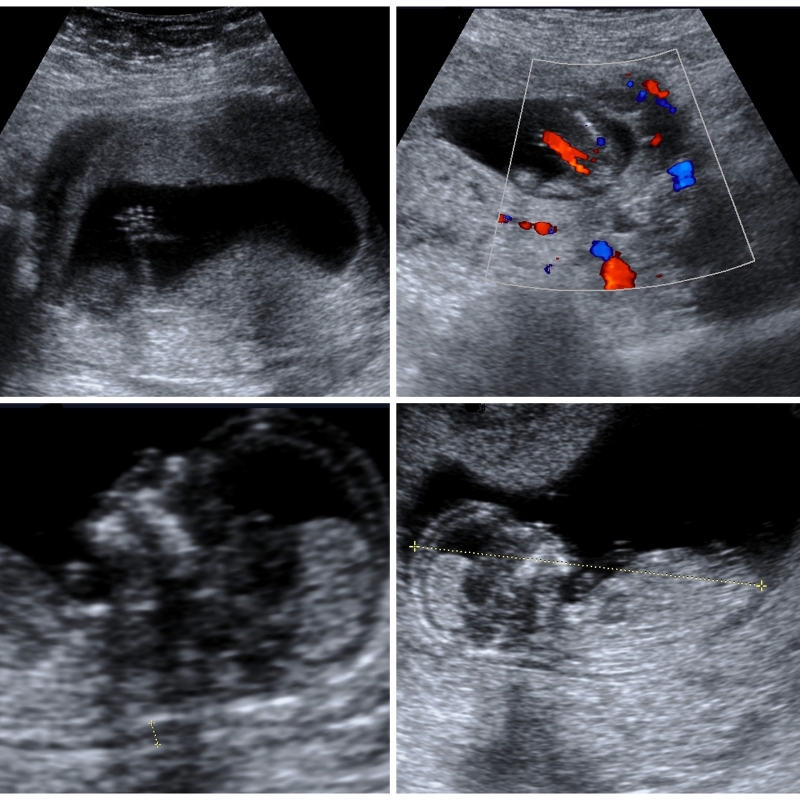

During the first trimester ultrasound, we closely examine the gestational sac, measure the embryo’s size, and check for the presence of a heartbeat. This crucial scan helps identify any potential issues early on, enabling timely medical intervention if needed. Our skilled sonographers are trained to perform this examination with precision, providing you with the necessary information and reassurance.

In the second trimester, our foetal morphology ultrasound offers a comprehensive view of your baby’s development. This detailed scan provides a close look at your baby’s anatomy, ensuring healthy growth and identifying any potential anomalies.

Our advanced ultrasound technology allows us to examine your baby’s organs, bones, and other structures in detail. We take great care to ensure all aspects of your baby’s development are thoroughly assessed, giving you peace of mind as you prepare for the next stages of your pregnancy journey.

Our detailed fetal morphology scans provide a comprehensive view of your baby’s anatomy, allowing us to detect potential anomalies and ensure your baby’s healthy development.